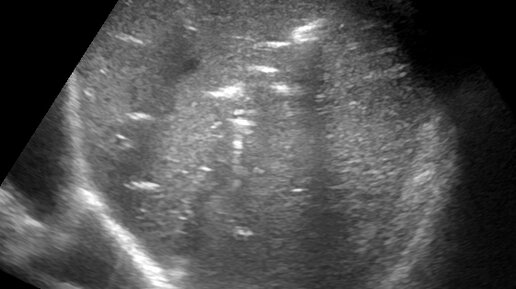

Аэробилия

Анамнез: пациент с холедохолитиазом. Выполнено эндоскопическое исследование (ФГДС) , папиллосфинктеротомия и извлечение камней из холедоха. Контрольное исследование на следующий день после выполненной манипуляции. При ультразвуковом исследовании печени, по ходу внутрипеченочных желчных протоков определяются множественные скопления газа с дистальными артефактами "хвост кометы" и дистальными акустическими тенями. Указанные скопления газа свободно смещаются при перемене положения тела пациента, при дыхании, а также, при умеренной компрессии датчиком...